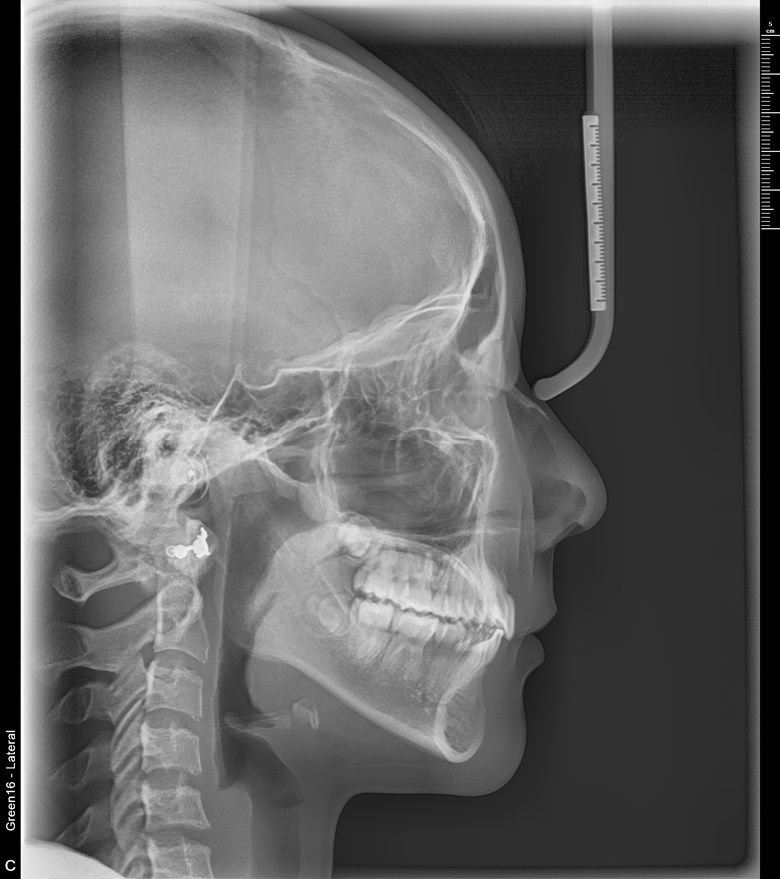

치료 후 사진입니다.